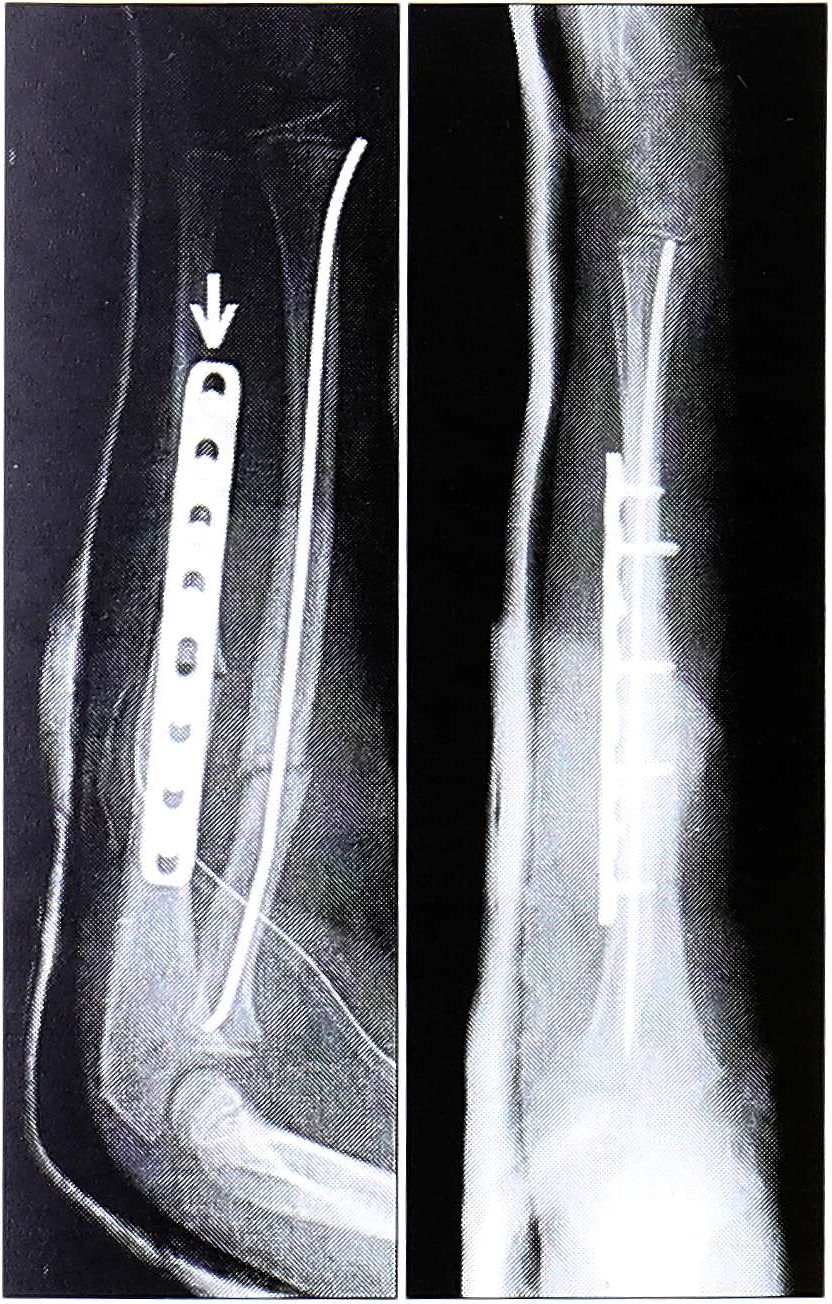

- Поскольку механические характеристики пластины LCP не изменились по сравнению с DCP, для изгибания пластин вполне достаточно стандартных инструментов. Однако для предотвращения деформации резьбовой части комбинированного отверстия рекомендуется вводить два резьбовых «держателя пространства» в отверстия, расположенные непосредственно рядом с местом изгибания пластины. При диафизарных переломах порозной кости может оказаться полезным моделирование прямых пластин последовательно на нескольких уровнях с созданием «волнообразной кривизны». Введенные блокирующиеся винты имеют разную инклинацию и фиксируются в кости с определенным интервалом, что обеспечивает более высокую устойчивость к вырывающим нагрузкам (рис. 4).

Рис. 4. Прямые LCP пластины можно изгибать последовательно на нескольких сегментах для создания волнообразной поверхности, что обеспечивает различную инклинацию винтов и большую устойчивость к вырывающим нагрузкам.